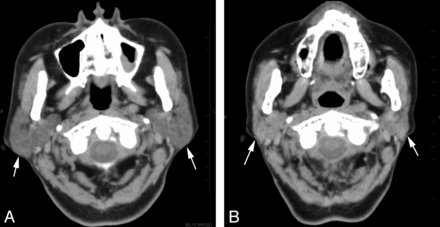

The reduction volume (mean ± SD, 95% confidence interval) in the submandibular gland after RIT, depending on the grade of scintigraphy, was 4.0 ± 3.1% (2.0%–6.1%) for grade 1 (n = 11); 14.7 ± 9.2% (10.8%–18.5%) for grades 2 and 3 (n = 24); and 42.3 ± 11.3% (28.3%–56.3%) for grade 4 (n = 5) (Figs 4 and 5). The submandibular gland volume after the treatment significantly decreased with an increase in the grade of dysfunction on scintigraphy (P < .001, 1-way analysis of variance). There was a significant difference in the reduction volume between grade 1 and grades 2 and 3 (P < .001), grades 2 and 3 and grade 4 (P < .001), and grade 1 and grade 4 (P < .001) groups, as determined by the Tukey Honestly Significant Difference test (Fig 3).

A 46-year-old woman who underwent 2 radioiodine treatments shows mild dysfunction of the submandibular gland on scintigraphy. Non-contrast-enhanced CT images (A) before and (B) after the treatment. The bilateral submandibular glands (arrows) show a mild volume reduction of 11% and an increase in attenuation of 12 HU on CT after the treatment.

A 68-year-old woman who underwent 4 radioiodine treatments shows severe dysfunction of the submandibular gland on scintigraphy. Non-contrast-enhanced CT images (A) before and (B) after the treatment. The bilateral submandibular glands (arrows) show a prominent volume reduction of 56% but a minimal increase in attenuation of 14 HU on CT after the treatment.

The attenuation change (mean ± SD, 95% confidence interval) in the submandibular gland after RIT, depending on the grade of scintigraphy, was 4.4 ± 3.5 HU (2.0–6.7 HU) for grade 1 (n = 11); 5.3 ± 5.9 HU (2.8–7.8 HU) for grades 2 and 3 (n = 24); and 10.2 ± 2.8 HU (6.8–13.7 HU) for grade 4 (n = 5) (Figs 4 and 5). In the submandibular glands, there was no significant correlation between the attenuation change and the grade of dysfunction on scintigraphy. No significant differences were noted among the attenuation changes for each group (Fig 6).